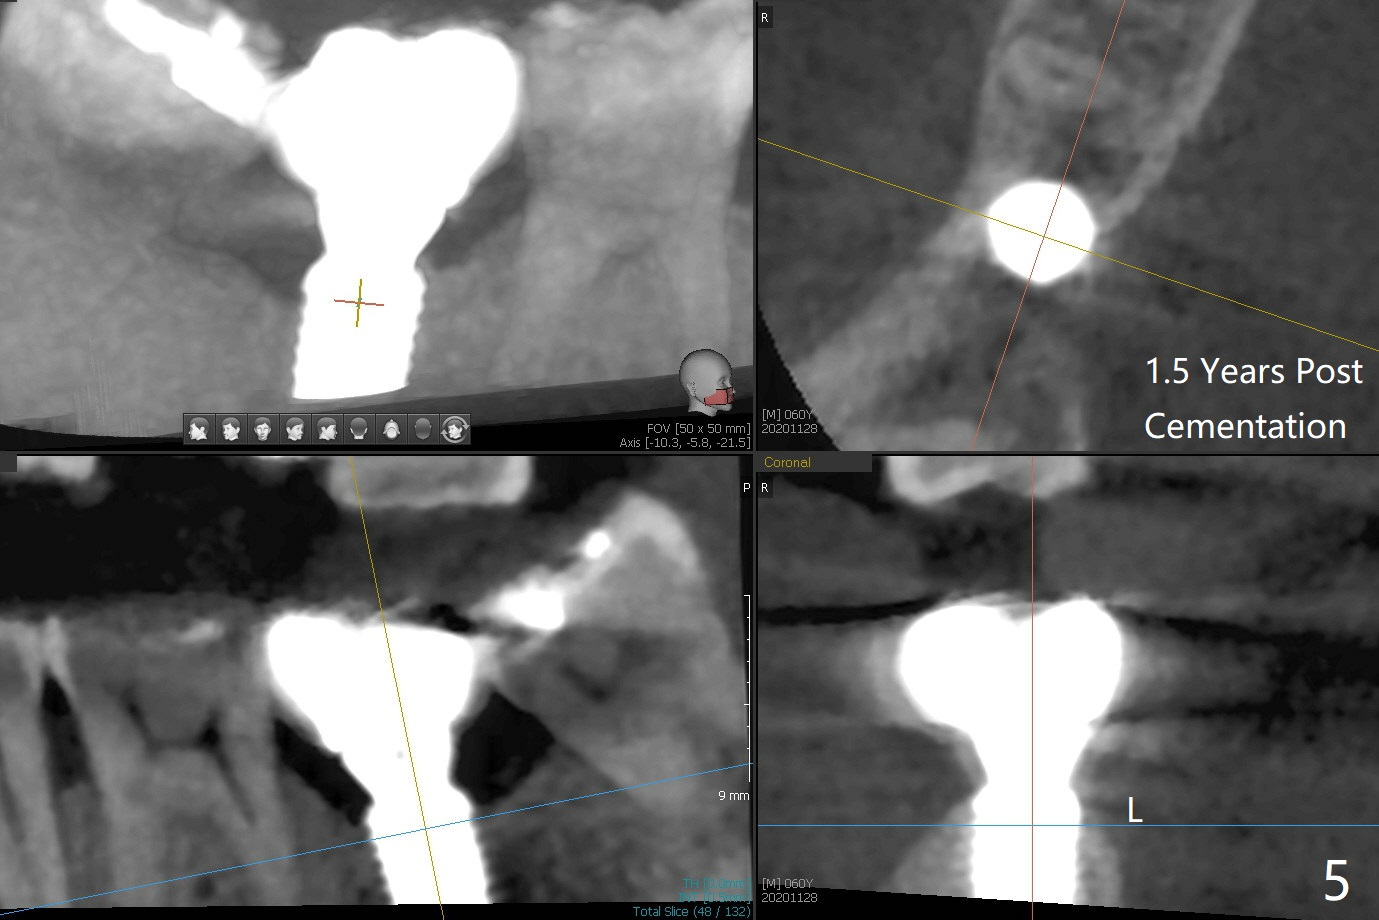

In fact 5x10 mm implant placement with guide requires using 5 mm cortical tap (Fig.1). When a 6x4 mm healing abutment is placed slightly supragingival, the clearance with the opposing supraerupted tooth is ~ 2 mm. It suggests that orthodontic intrusion is required for restoration. In fact the patient is incompliant with orthodontic mini-implant placement and retraction. When the implant at #31 is osteointegrated 4.5 months postop (Fig.2), it is used an anchor with an abutment and a provisional to intrude the opposing tooth. The final crown is cemented 10 months postop (Fig.3) with occlusal clearance (Fig.3' *). The contacts between #2 and 3 and between #31 and 32 are loose with papillary inflammation 5 months post cementation. It is planned to remove #31 crown/abutment for pick up impression/porcelain addition. Instead the crown is removed. After removing #32 MO composite with minor 2nd caries, new composite is placed (Fig.4 *) while the crown is reseated. When the crown is recemented, bitewing shows open margin (Fig.4), but the contact is wide and tight. After occlusal adjustment, occlusal contact at #31 and 32 mesial is heavier than that at #30. #3 crown is recommended. The occlusal table difference betweeen the upper 1st and 2nd molar is ~ 2 mmm preop (Fig.4'), whereas the difference is ~ .6 mm postop (in combination of occlusal equilibrium and intrusion of the upper 2nd molar (Fig.4)). It seems that orthodontic intrusion is not efficient in a male with bruxism. There is mild lingual (L) and distal bone loss 1.5 years post cementation (Fig.5) when CT is taken for #3 immediate implant. Lower Molar Immediate Implant, Armaments Xin Wei, DDS, PhD, MS 1st edition 07/12/2018, last revision 11/28/2020